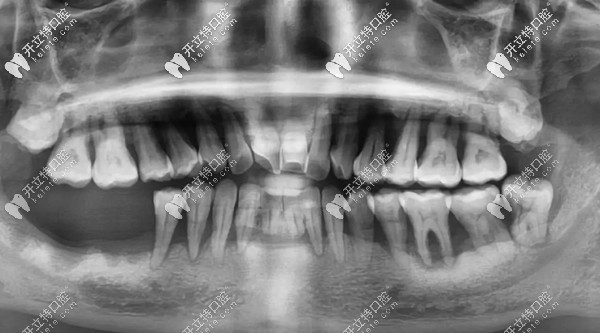

【新桥口腔王峰医生的诊断】

邓老师的主诊医生王锋表示:“楔形缺损和四环素牙会使牙齿对外界刺激变得敏感,但让全口牙齿松动,一吃东西就痛的“元凶”,其实是长年得不到治疗的牙周病。”